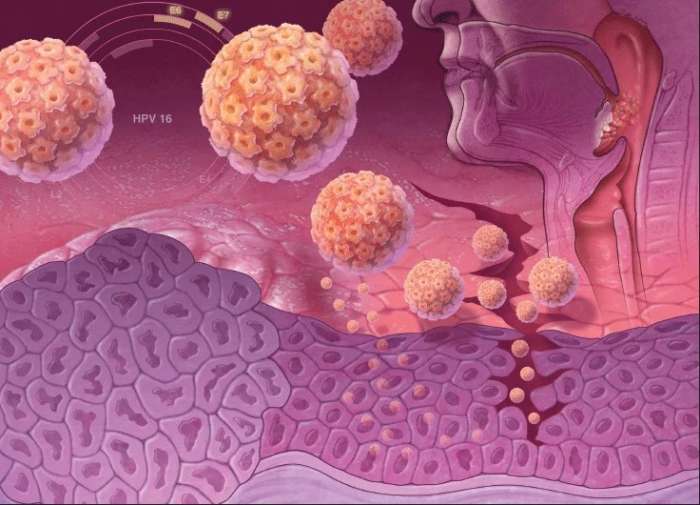

Факторы Риска ВПЧ: Визуальный Обзор и Информация